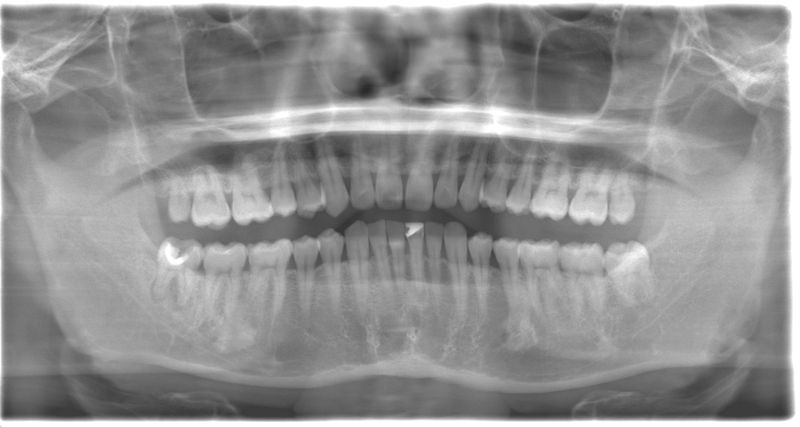

CASE 1

| 年齢・性別 | 30代・女性 |

| 主訴 | 左右に分けて親知らずを抜きたい、できれば痛くなく抜きたい |

| 親知らずのはえ方 | 完全に出ていてまっすぐはえている |

| 抜歯期間 | 15分 |

| 抜歯費用 | 約2,000円(保険内) |

| 抜歯内容 |

何度か虫歯になり痛みはないが早めに抜きたい。 完全に頭が出ているため歯ぐきを切ったり骨を削らずに抜歯しました。 根の形も単純なため抜歯自体は5分もかからず上下ともに終わりました。 術後痛みや腫れも出ていません。 抜歯後は感染をしやすいため必ず抗生物質を飲み切ってください。 |